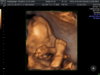

Klaudia_i_nikodem

Fanka BB :)

@Gosam , łożysko migruje do 30 tc więc niepowiedziane, że będzie tak źle. Ja mam przodujące nisko, dzisiaj o tym rozmawiałam z gin, niby nic to nie oznacza strasznego na tym etapie, oprócz tego, że trzeba zwolnić tempo, ze współżyciem też trzeba uważać, etc. 12 stycznia będę mieć kontrolę, zobaczymy czy się coś dźwignie.